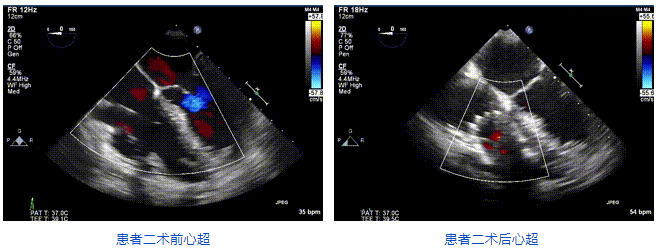

2021年12月24日,復(fù)旦大學(xué)附屬中山醫(yī)院葛均波院士團(tuán)隊(duì)成功應(yīng)用LuX-Valve Plus為一例極重度三尖瓣反流(TR)合并房顫、房缺的患者完成了經(jīng)血管三尖瓣置換術(shù),這是在前基礎(chǔ)上,本周完成的第三例經(jīng)血管三尖瓣置換手術(shù),葛均波院士、周達(dá)新教授等與心外科魏來教授、賴顥教授,心超室的潘翠珍教授、李偉教授及麻醉科的郭克芳教授共同完成了本周手術(shù),均獲得圓滿成功!患者術(shù)后超聲顯示無TR,臨床癥狀明顯改善。本周手術(shù)的成功也為LuX-Valve Plus救治性臨床研究添上了濃墨重彩的一筆。

三例患者入院后,葛均波院士團(tuán)隊(duì)周達(dá)新教授、潘文志教授、張?jiān)床┦?、陳莎莎博士及心超室的潘翠珍教授、李偉教授對患者的情況進(jìn)行詳細(xì)評估和討論,最終決定為三例患者選擇LuX-Valve Plus40mm、50mm和50mm型號(hào)的瓣膜進(jìn)行手術(shù)治療。手術(shù)后即刻拔除氣管插管,術(shù)后患者三尖瓣反流癥狀得到顯著改善,復(fù)查心超結(jié)果顯示人工三尖瓣瓣膜支架固定穩(wěn)定,瓣葉關(guān)閉形態(tài)未見異常,未見明顯反流。